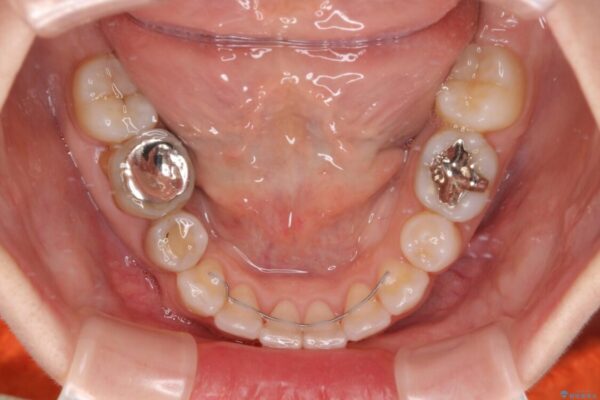

治療途中

• 【モニター】出っ歯と咬み合わせを改善 ワイヤー装置の抜歯矯正 治療途中画像

奥歯の咬み合わせ改善には1年ほどの期間と処置中の噛みにくさを強いることとなりましたが、抜歯後はスムーズに治療を完了させることができました。